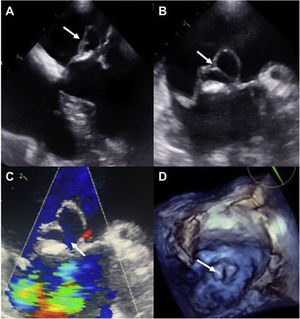

This is the case of a 67-year-old male with constitutional syndrome, fever, dyspnea, and a systolic-diastolic aortic murmur. The echocardiogram revealed the presence of aortic vegetation and a large pseudoaneurysm of anterior mitral valve location (Fig. 1-arrows) without valvular or peri-annular involvement, and positive blood cultures for Streptococcus salivaris. With a diagnosis of acute endocarditis, mitral-aortic replacement was performed under extracorporeal circulation. The left atriotomy revealed the presence of a violet giant pseudoaneurysm (Fig. 2A and B) of the entire serosanguineous anterior mitral valve (Fig. 2C and D). The postoperative period was uneventful with negative valve cultures. The association between a pseudoaneurysm post-endocarditis isolated from the anterior mitral valve leaflet without damage to the valve or mitral-aortic continuity is a rare finding. The echocardiogram is key here to select treatment and the optimal surgical time.